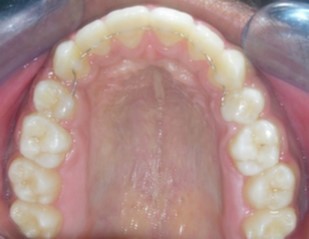

Intraoral assessment. (Figure 1d,Figure 1e,Figure 1f,Figure 1g,Figure 1h).

Figure 1g.Pre-treatment intra-oral-Upper occlusal

Figure 1h.Pre-treatment intra-oral-Lower occlusal

The maxillary arch was V-shaped with severely proclined and rotated maxillary incisors with a palatally placed 12. The mandibular arch was U-shaped with severe crowding of mandibular incisors, with 43 partially erupted and buccally placed with transpositioned 42 and 43, with 42 mesiolingually rotated, 33 distolingually rotated and 34 distolingually rotated and buccally placed.

Severe increase in overjet and deep bite were both observed. The maxillary midline coincided with the skeletal midline but the mandibular midline was shifted to the right side by 1 mm. Bilateral maxillary posterior crossbite was also observed. On right side the molar relation was Class I and on the left side it was Class II. The canine relation was Class II on the left side and the curve of Spee was increased.